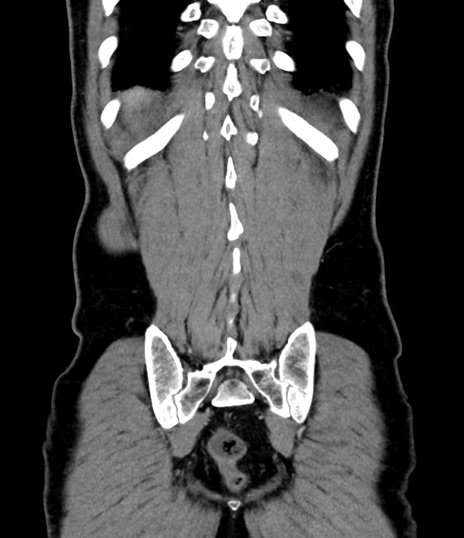

症例8(冠状断像)

【症例】 60歳代男性

【主訴】 黒色吐物

【現病歴】 4日前から嘔気自覚、2日前の朝食後にも嘔気あり、自分で手で嘔吐反射起こし嘔吐したところ血が混ざっていたため受診。

【既往歴】 5年前汎発性腹膜炎を伴う急性虫垂炎で手術、高血圧、前立腺肥大症、高脂血症

【身体所見】 腹部正中に手術癩痕あり 腹部平坦・軟圧痛なし膨満感あり

【データ】WBC 8400、CRP 4.54